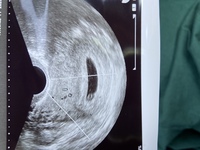

2 妊娠初期に見える胎嚢とは? 3 胎嚢はいつから見えるの?確認できる時期 31 妊娠する前なのに妊娠1日目になる!妊娠週数の数え方; 4週の後半頃から胎嚢が見えることもありますが、まだ小さくて確認出来ないことも珍しくありません。 妊娠5週 月経の遅れから、お母さんが妊娠に気付き始める頃です。 早ければつわりの症状も出てくるので、先につわりで気が付くお母さんもいます。 心拍確認はいつ?何週目でできた?体外受精の場合 結果!無事、心拍確認できました(tt) 心拍確認できたのは、 7週目5日目 でした。 早いと6週目くらいからできるみたいですが、私はhcgの上昇が遅かったこともあり7週5日目でもギリギリくらいだったと思います。

いつもお世話になってます。先週陽性反応が出た者です。今日、またエコーを取ってきたのですが、10/3 17mm (4w2dと言われた)10/9 109mm(今日 5w1dのはず)で、胎芽が見えませんでした(涙)。皆さんはいつ頃胎のうがどのくらい胎嚢確認や心拍確認はいつから?先輩ママの体験談も産婦人科医監修|Milly ミリー そして価格も抑えて生まれ変わりました。 胎嚢が絨毛膜に分化を始めるに従い、胎嚢の中には骨や身体の器官が発達途上の「胎芽」が確認できます。 胎嚢は最速でいつ見えるの? 妊娠4週2日が最速 といわれています。 ここで注意! これは 胚移植を伴う体外受精・顕微授精の人だけ の話ですよ! いくらタイミングや人工授精で排卵日が確定しているからといって、絶対確実ではない胚移植以外の方には

胎嚢を確認するには時期が早すぎたということがあります。 胎嚢は一般的には 妊娠4週末から 見えるので、初診で確認できなかった時に「週を明けて再度来院してください」といわれるのはこのためです。 胎嚢や胎芽はいつから見える?平均は? 胎嚢確認ができる時期はいつ? 早い人は、妊娠4周ごろ から確認できます。 通常であれば、 遅くとも6週まで には確認できるようになります。 初診が、妊娠5週後半~6週以降(生理開始予定日から10日~14日たったころ)であれば、その場で確認できる